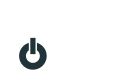

A Secretaria de Meio Ambiente, Habitação e Desenvolvimento Urbano de Ribeirão Pires, por meio do Departamento de Gestão Ambiental, realizará entre os dias 6 e 31 de março, uma ação para recolhimento de chapas de raio-x.

O material poderá ser entregue na base do departamento que está localizado na rua João Domingues Oliveira, 320, no Centro. Os filmes radiográficos quando descartados de forma irregular são nocivos ao meio ambiente, podendo contaminar o solo e causando desde anemia até problemas neurológicos em quem o manuseia. Por outro lado, quando destinado corretamente, é possível obter prata de um e também resíduos plásticos das chapas, que contém acetato na sua composição, podendo ser reutilizado na indústria.

“Campanhas como essas visam diminuir os impactos do descarte incorreto, já que esses materiais são extremamente tóxicos para todo o tipo de vida. Por esse motivo sempre incentivamos a reciclagem, para proteger o meio ambiente e também a nossa saúde”, explicou a secretária Andreza Araújo.

Entrega de chapas de raio-x para reciclagem

De 06 até 31 de março

Das 8h às 17h

Departamento de Gestão Ambiental – rua João Domingues Oliveira, 320 – Centro